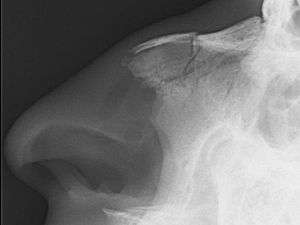

X-ray of nasal bone fracture